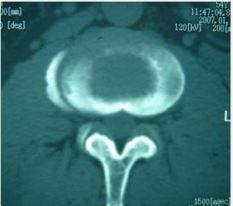

In 13 patients (18.57%), the bone at the edge of the vertebral body was stiffened like a bird’s beak, which was connected with the edge of adjacent vertebral body hyperplasia to form a bone bridge, and 11 patients (15.71%) had poor lumbar stability. CT showed 53 cases (75.71%) patients with vertebral edge disease have size about 2~6 mm multiple focal bone destruction, bone destruction around focal sclerosis of bone hyperplasia, bone of new born stove and new bone broken, the whole edge vertebral bodies like lace structure formation “lace vertebral (Figure 3)”; In 17 cases (24.28%), intervertebral disc lesions showed isodense shadows, articular cartilage surface sclerosis and hyperplasia, proliferated bony protruding toward the edge of the vertebral body to form “lip”-shaped osteophytes, anterior longitudinal ligament and paravertebral sides were calcified, and there were osteophytes connect (Figure 4); In this group, 18 patients (25.71%) had widened paravertebral muscles with abscess formation and clear surrounding space, but no abscess drainage imaging (Figure 5).

MRI showed that 70 patients with diseased vertebral bodies and intervertebral discs showed heterogeneous signals, in 18 cases, paraspinal features were thin and irregularly enhanced abscess walls and abnormal signals in poorly defined soft tissues, T1WI showed low signal, and T2WI showed high signal; Eleven patients had poor lumbar spine stability and spondylolisthesis; 42 patients showed uneven hypersignal in the vertebral body, intervertebral disc, and spinal canal on T1WI, T2WI, and fat pressure images, and the corresponding plane dura or nerve root compression (Figure 6).